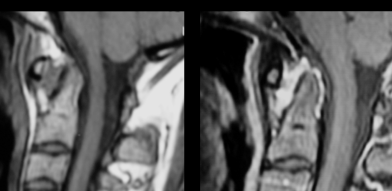

Rachis cervical

- Arthrite C0-C1, C1-C2

- Diastasis C1-C2 (Subluxation Atlanto-Axiale antérieure)

- Pannus C1-C2 hypervascularisé

- Erosions de l’Odontoide